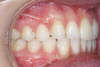

Canine incluse traitée avec des gouttières

Etapes intermédiaires